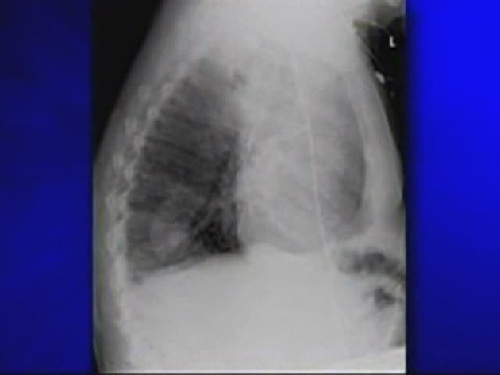

榮恩·斯維頓因肺中長出豌豆苗肺功能衰竭

????美國麻薩諸塞州男子榮恩·斯維頓最近一段時(shí)間總是咳嗽不止,身體日益衰弱。然而,為他治療的醫(yī)生卻一直找不到病因,他既沒有患上肺癌,也沒有長腫瘤。最終醫(yī)生從他肺部的X光透視片上發(fā)現(xiàn),居然有一棵豌豆苗在他的肺里生長。這粒豌豆在斯維頓的肺中發(fā)芽生根,長成了一棵近4厘米長的植物,導(dǎo)致他的肺功能衰竭。

X光片顯示出斯維頓肺中的豌豆苗